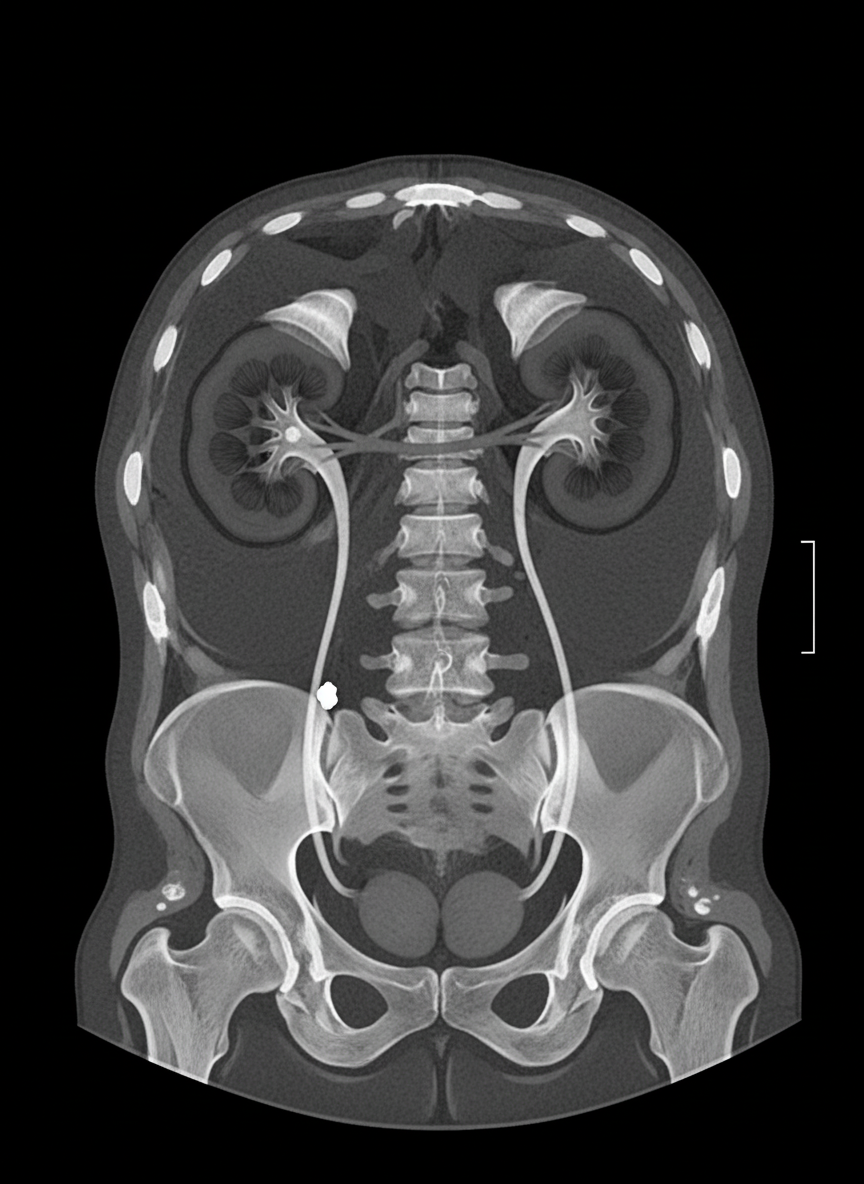

A 40-year-old male presented with severe pain in the left upper abdomen radiating to the groin. Urine routine examination shows 6-8 pus cells and 15-20 RBCs. A CT scan was performed. What is the most likely diagnosis?

Explanation: ***Left ureteric calculus*** - **Severe colicky pain** in the left upper abdomen radiating to the **groin** is classic for ureteric stone, following the path of the ureter. - **Hematuria** (15-20 RBCs) on urine analysis is a key finding, along with **pyuria** (6-8 pus cells) due to associated inflammation. *Aortic aneurysm* - Typically presents with **tearing back pain** radiating to the abdomen, not specifically to the groin. - **No hematuria** would be expected, and pain is usually constant rather than colicky. *Acute cholecystitis* - Pain is typically in the **right upper quadrant** radiating to the **right shoulder**, not to the groin. - **No hematuria** or pyuria would be present, and pain is usually related to **fatty meals**. *Acute colitis* - Presents with **diarrhea**, **blood in stool**, and **lower abdominal cramping**, not upper abdominal pain. - **No hematuria** would be expected, and pain doesn't radiate to the groin.